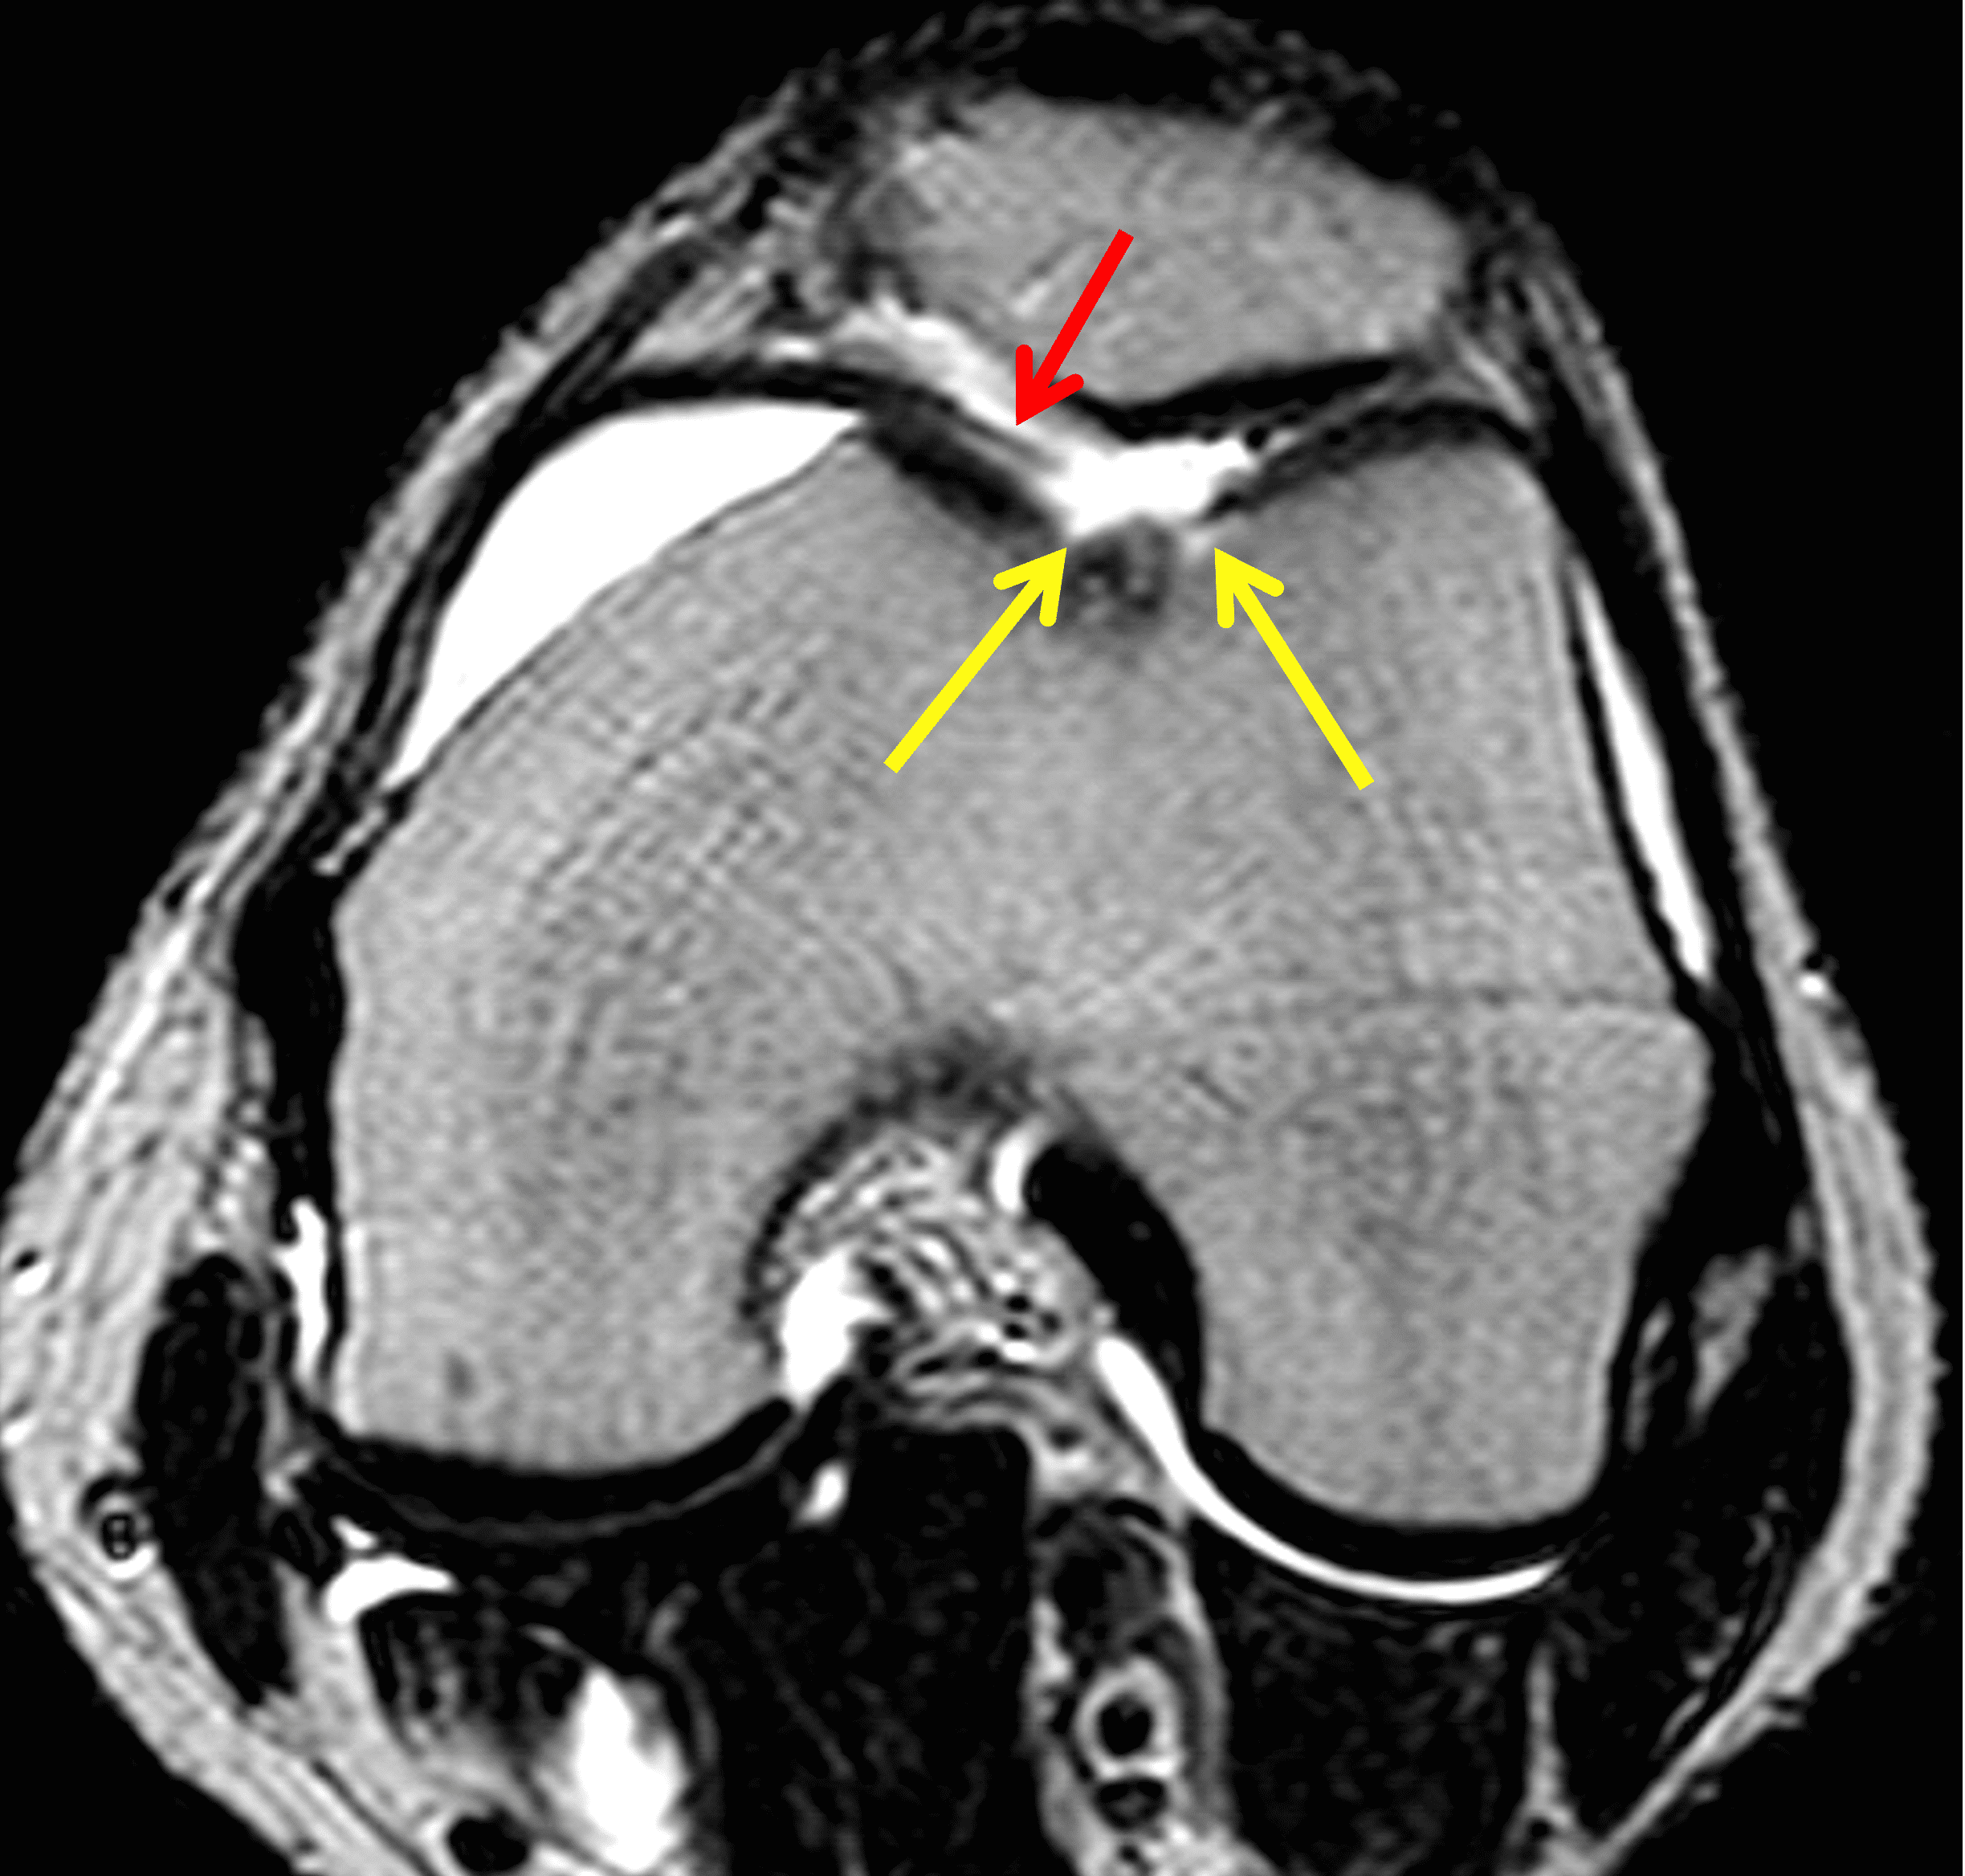

A 32-year-old man suffered a traumatic chondral injury to the medial femoral condyle that was treated with an osteochondral allograft 20 months previously. Representative images from a current knee MRI include (1A) coronal fat-suppressed fluid-sensitive and sagittal (1B) T1-weighted, (1C) proton density-weighted, and (1D) T2-weighted sequences. Are the post-operative MRI findings normal and expected, or abnormal and pathologic? Based on these images, would you characterize the procedure as a success or failure?

Figure 2: (2A) On the coronal image, the margins of the osteochondral graft are faintly visible (arrowheads). Both the graft and underlying bone show mild marrow edema, an expected finding. (2B) The T1-weighted image shows continuity of the marrow in the graft (asterisks) with the underlying bone, indicating osseous integration. A bioabsorbable pin (arrow) used for graft fixation is partly visible. (2C) The proton density-weighted image shows a low signal intensity seam (black arrow) between the native cartilage and transplant, as well as a defect in the subchondral bone plate of the graft (red arrow) where the pin was drilled, both normal findings. (2D) The T2-weighted image shows a smooth, congruent articular surface (arrows), restoring the normal anatomy, and a tiny subchondral cyst. No findings are present to suggest graft failure. The patient’s current symptoms were attributed to pathology elsewhere in the joint (not shown).